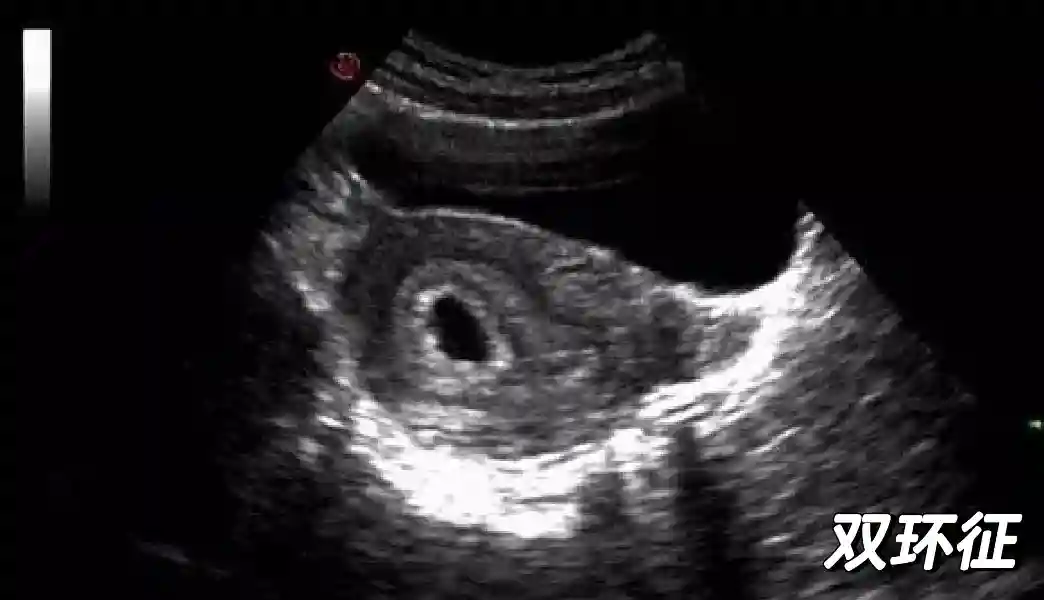

1??妊娠囊:早期妊娠囊:正常妊娠囊位于宮腔上段,表現(xiàn)為宮腔內(nèi)圓形或橢圓形的無(wú)回聲區(qū),周邊為完整的、厚度均勻的強(qiáng)回聲環(huán),強(qiáng)回聲環(huán)厚度≥2mm,強(qiáng)回聲是妊娠絨毛的回聲,隨著妊娠囊的增大,形成特征性的“雙環(huán)征” ,10周以后消失。正常的妊娠囊增長(zhǎng)速度是平均 1 mm /d。